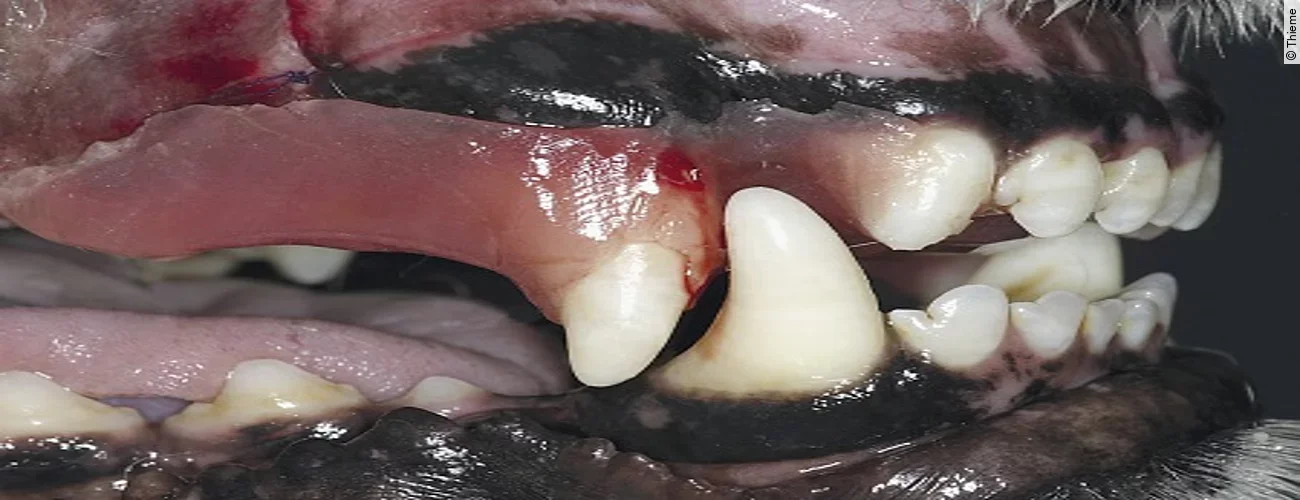

Finales Stadium der Luxation eines Zahnes ist dessen vollständiger Verlust, die Avulsion. Ist der herausgeschlagene Zahn intakt, so kann mittels Replantation eine Wiederherstellung der ursprünglichen Okklusion erreicht werden.

Replantation nach Avulsion Oberkieferfangzahn rechts

Der Originalartikel „Avulsion Oberkieferfangzahn rechts“ stammt aus dem Bild-Atlas der Zahnbehandlungen Hund und Katze; 2. aktualisierte Auflage; 2022.